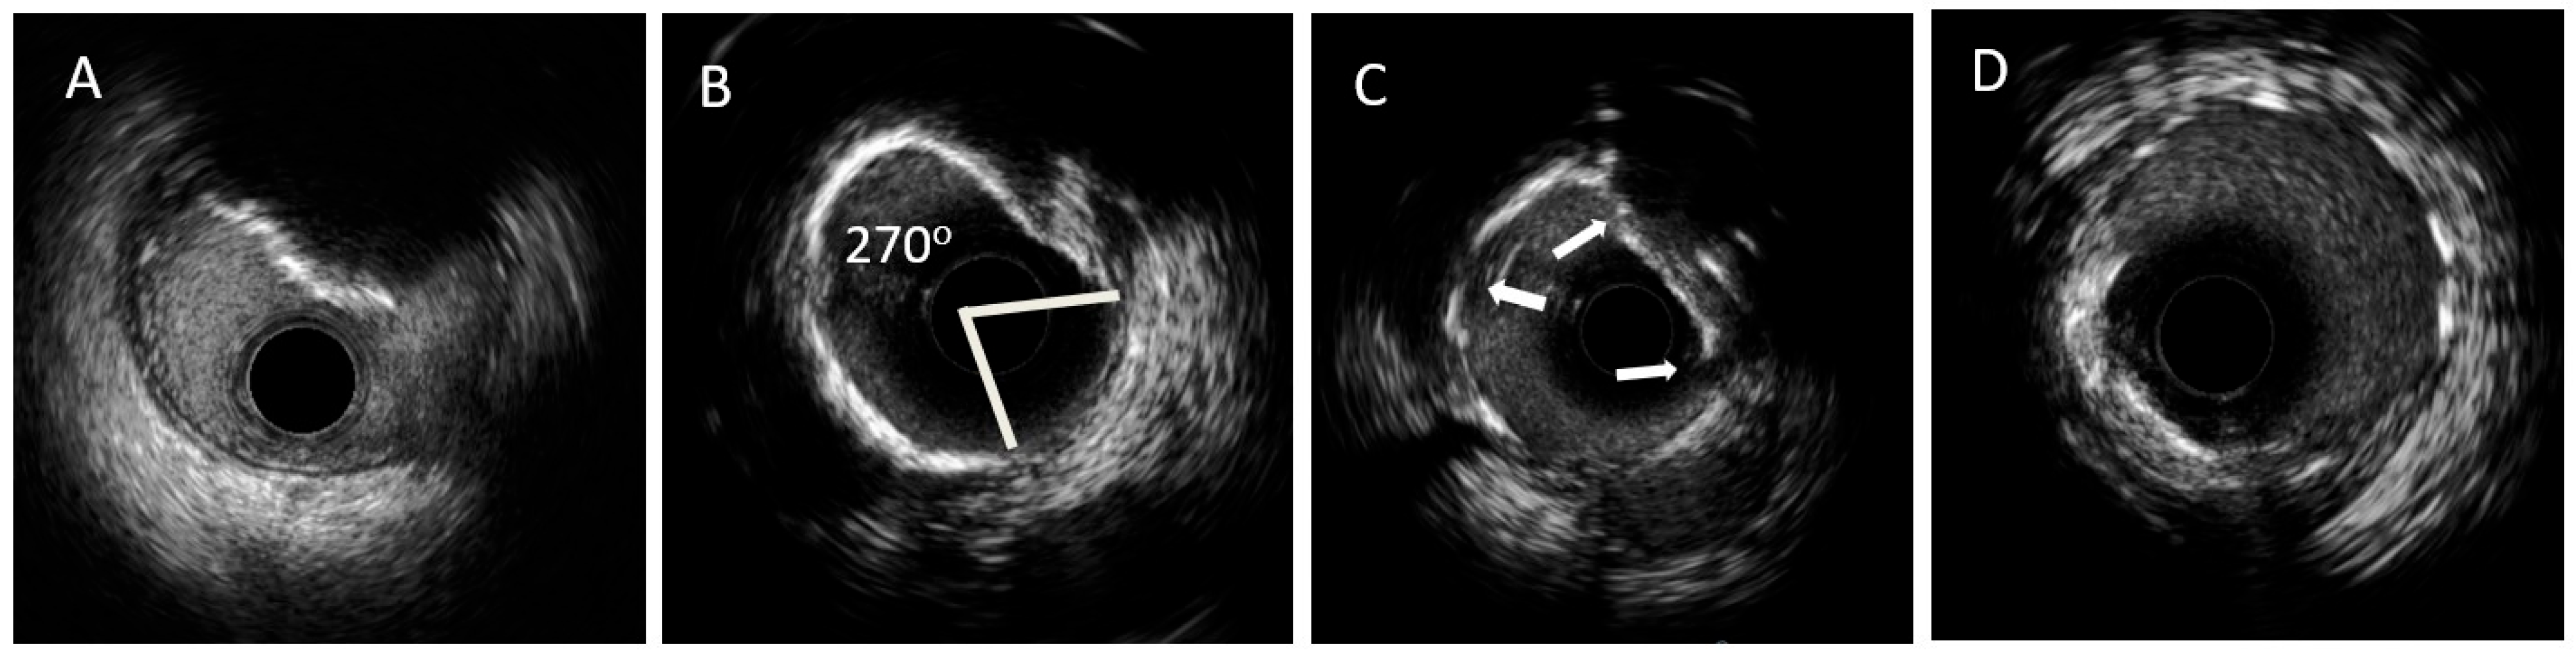

| Criteria of calcium severity and risk of stent underexpansion indicating the need for lesion modification | Superficial calcium angle of >270° (longer than 5 mm) 360° angle of superficial calcium Calcified nodule Vessel diameter ≤ 3.5 mm | Calcium max angle > 180° Calcium max thickness > 0.5 mm Calcium length > 5 mm |